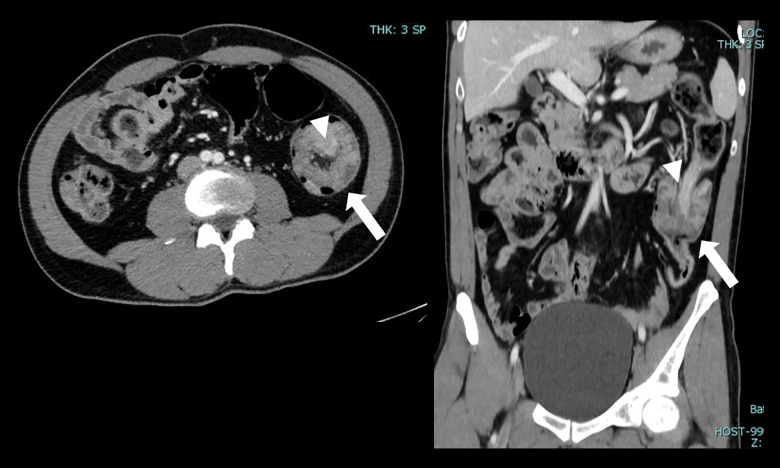

成人肠套叠(AI)是一种罕见的疾病,具有多种临床表现和管理挑战。尽管罕见,但了解其流行病学,临床特征和区分良恶性导点的预测因素对有效治疗至关重要。本研究旨在评估病理性人工智能患者的人口学和临床特征,并探讨与恶性导点相关的因素。材料与方法回顾性分析2014年1月1日至2024年1月1日诊断为AI的bb0 ~ 18岁患者的病历。根据肠套叠的部位和病因对患者进行分类。评估恶性导点的预测因素,包括年龄、性别、表现症状、位置和肠套叠大小。复习计算机断层扫描(CT)图像以确认诊断。排除短暂性小肠肠套叠及饲管相关肠套叠。结果10年内共发现病理性人工智能26例,男性占69.2%,平均年龄53.3岁。腹痛是最常见的症状(65.4%),诊断为肠梗阻的病例占23.1%。CT扫描是主要诊断方式(92.3%)。结肠肠套叠最为常见(53.8%),手术治疗较为常见(69.2%)。组织病理学检查显示大多数病例(57.7%)为良性铅点,以脂肪瘤和息肉最为常见。直肠出血与恶性导点显著相关(P=0.011)。结论人工智能具有多种临床特征。它主要影响结肠。直肠出血提示恶性铅点的可能性较大。多学科方法对于最佳的基于病例的管理至关重要。

BACKGROUND Adult intussusception (AI) is a rare condition with diverse clinical presentations and management challenges. Despite its rarity, understanding its epidemiology, clinical features, and predictive factors distinguishing benign and malignant lead points is crucial for effective management. This study aimed to assess the demographic and clinical characteristics of patients with pathological AI and examine factors associated with malignant lead points. MATERIAL AND METHODS Medical records of patients aged >18 years with diagnosis of AI between January 1, 2014, and January 1, 2024 were retrospectively analyzed. Patients were classified based on location and etiology of intussusception. Predictive factors for malignant lead points were assessed, including age, sex, presenting symptoms, location, and size of intussusception. Computed tomography (CT) scan images were reviewed for diagnosis confirmation. Transient small bowel intussusceptions and intussusceptions related to feeding tubes were excluded. RESULTS Twenty-six cases of pathological AI were identified over 10 years, with a male predominance (69.2%) and a mean age of 53.3 years. Abdominal pain was the most common presenting symptom (65.4%), with bowel obstruction diagnosed in 23.1% of cases. CT scans were the primary diagnostic modality (92.3%). Colocolic intussusceptions were most prevalent (53.8%), and surgical management was common (69.2%). Histopathological examination revealed benign lead points in the majority (57.7%) of cases, with lipomas and polyps being the most common. Bleeding per rectum was significantly associated with malignant lead points (P=0.011). CONCLUSIONS AI presents with diverse clinical features. It predominantly affects the colon. Bleeding per rectum indicates a higher likelihood of malignant lead points. A multidisciplinary approach is essential for optimal case-based management.